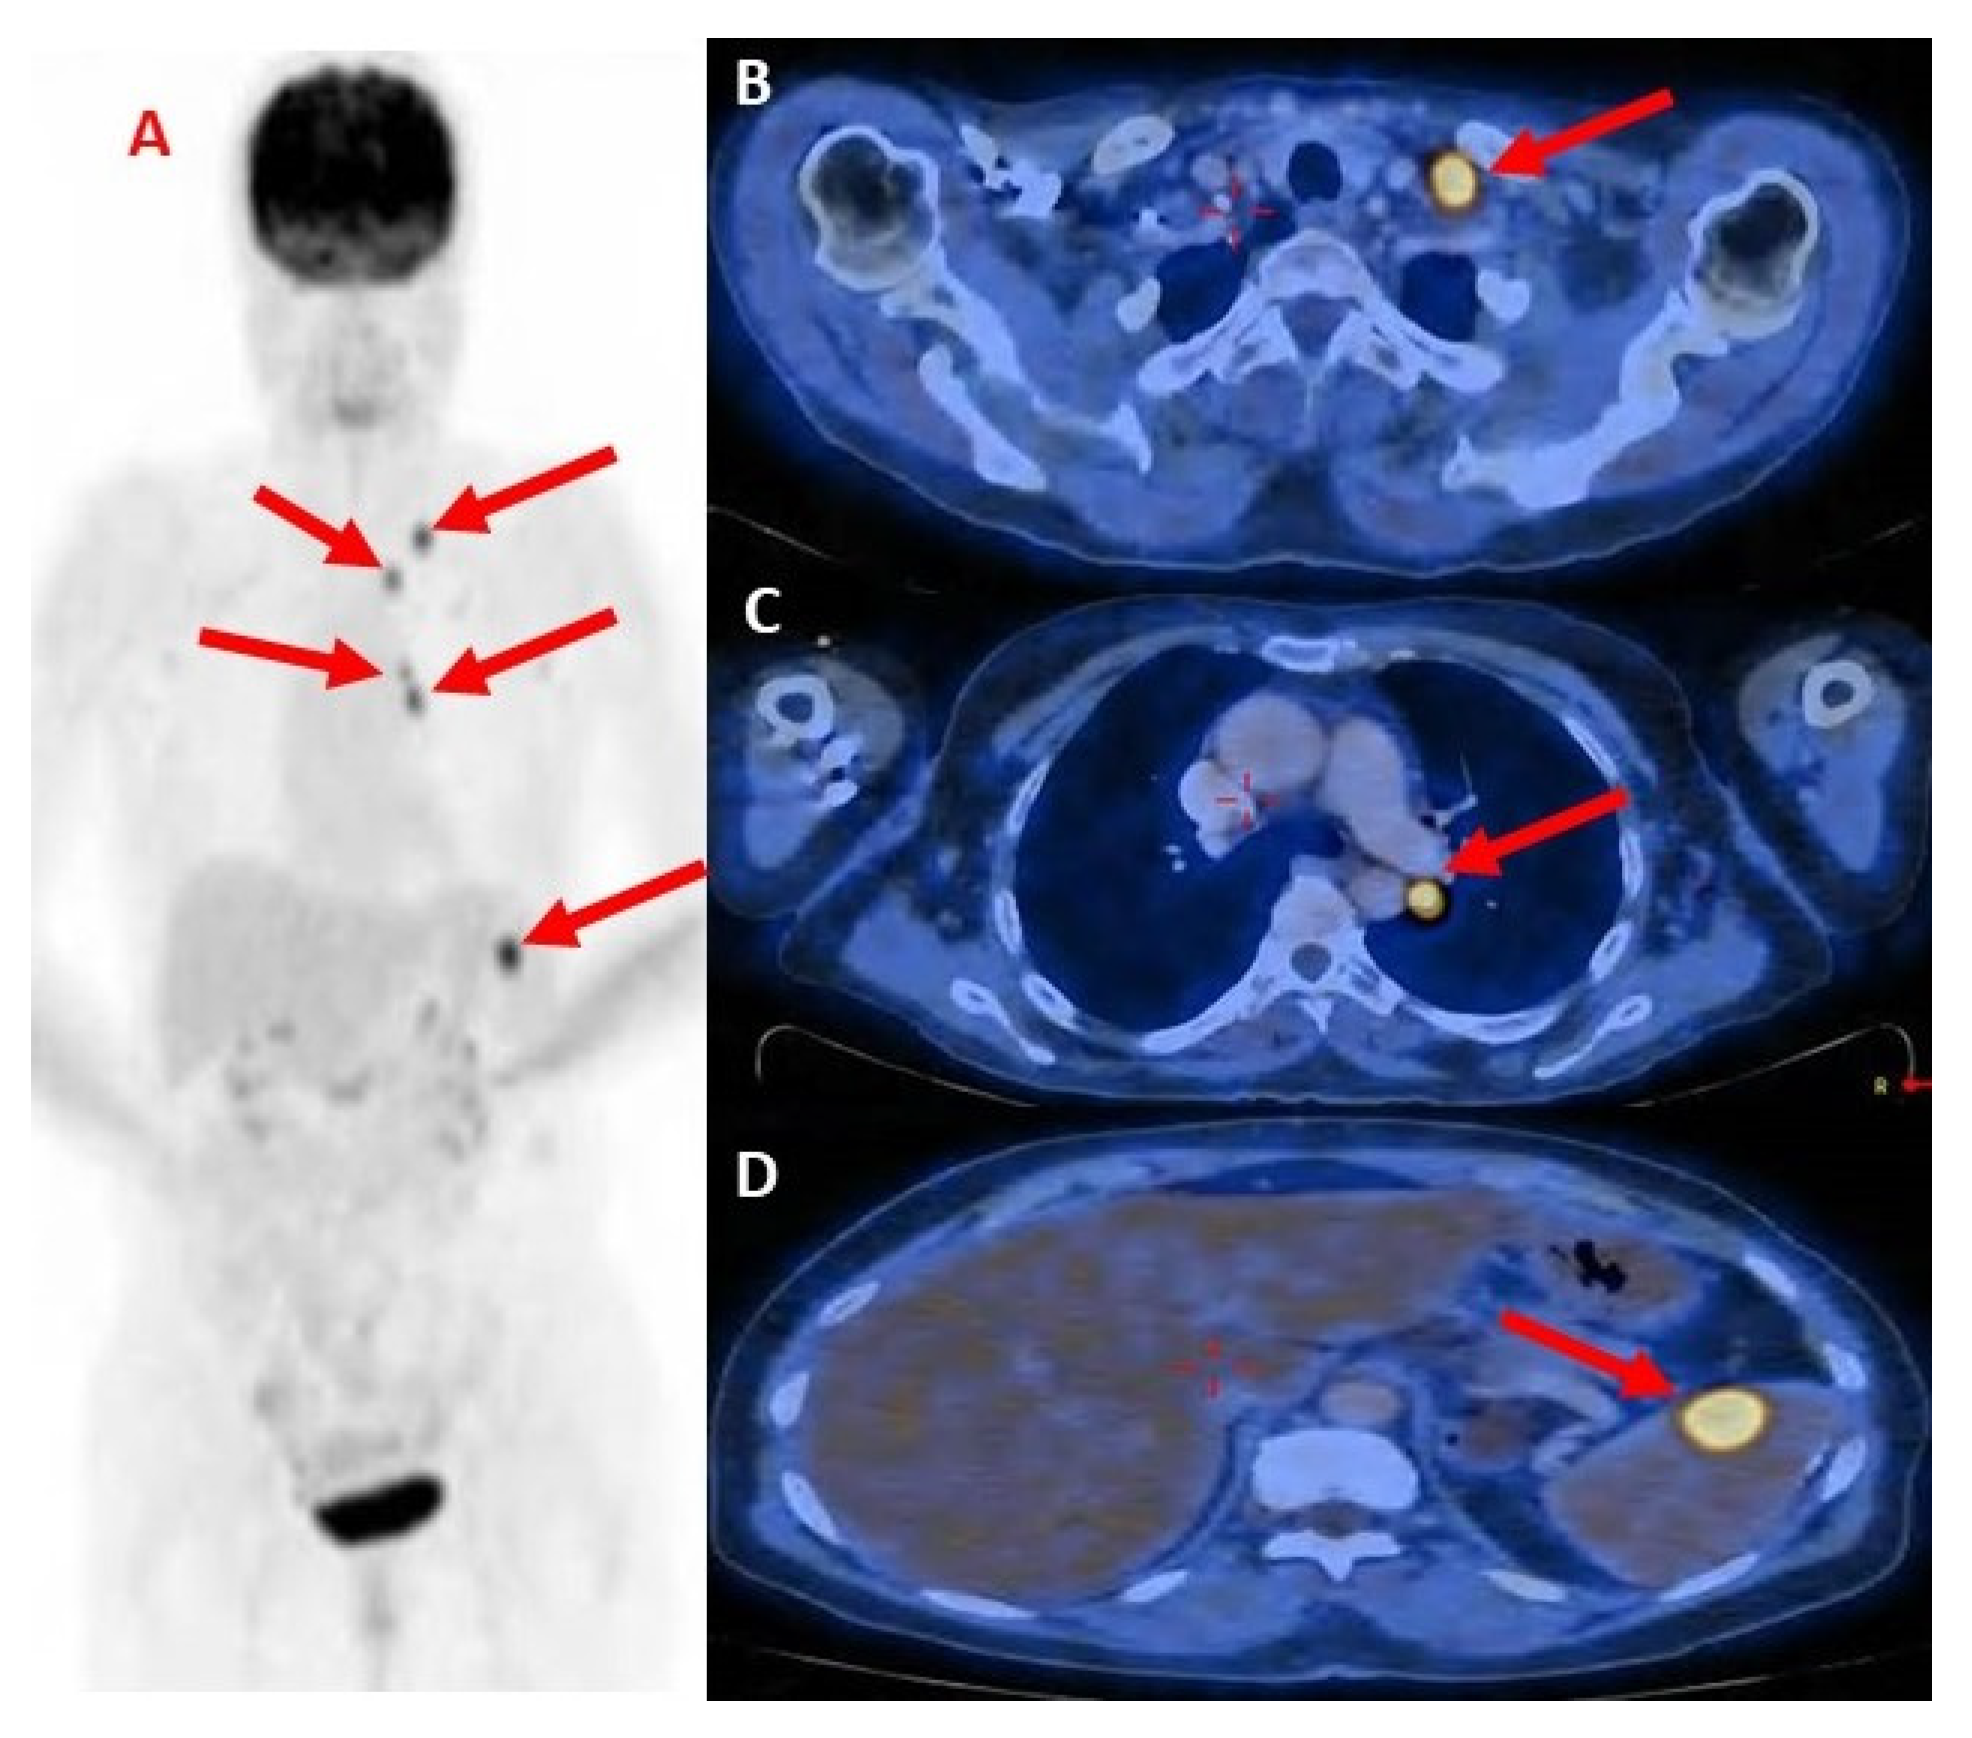

Following one month of Osimertinib administration (80 mg once a day), the patient’s dermatological symptoms improved, and two months later a PET-CT showed a radiological significant response (Figure 4). The left supraclavicular lymph nodes had receded in diameter with no pathological uptake. The mediastinal lymph nodes and the hilum of the left lung returned to normal size and were without pathological uptake. The LUL lesion had receded with lower pathological uptake. The splenic lesion had decreased in size without pathological uptake. (High muscle absorption was demonstrated due to a lack of fasting as required).

Figure 4.

PET-CT showing complete radiologic response to Osimertinib treatment.